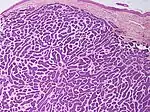

Basal-cell carcinoma cells appear similar to epidermal basal cells, and are usually well differentiated.[25]

Nodular basal-cell carcinoma (also known as "classic basal-cell carcinoma") accounts for 50% of all BCC.[27] It most commonly occurs on the sun-exposed areas of the head and neck.[28]: 748 [29]: 646 Histopathology shows aggregates of basaloid cells with well-defined borders, showing a peripheral palisading of cells and one or more typical clefts.[27] Such clefts are caused by shrinkage of mucin during tissue fixation and staining.[30] Central necrosis with eosinophilic, granular features may be also present, as well as mucin. The heavy aggregates of mucin determine a cystic structure. Calcification may be also present, especially in long-standing lesions.[27] Mitotic activity is usually not so evident, but a high mitotic rate may be present in more aggressive lesions.[27] Adenoidal BCC can be classified as a variant of NBCC, characterized by basaloid cells with a reticulated configuration extending into the dermis.[27]

Cleft.

Cleft.